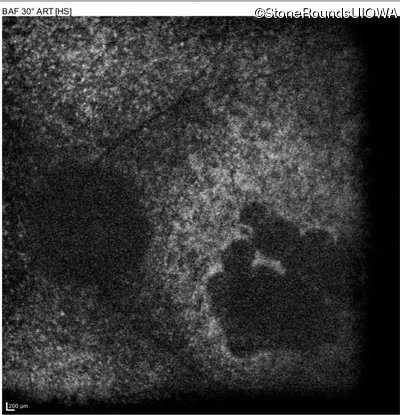

Blue Autofluorescence - Right - 5/400

Exemplar

Blue Autofluorescence - Left - 10/300